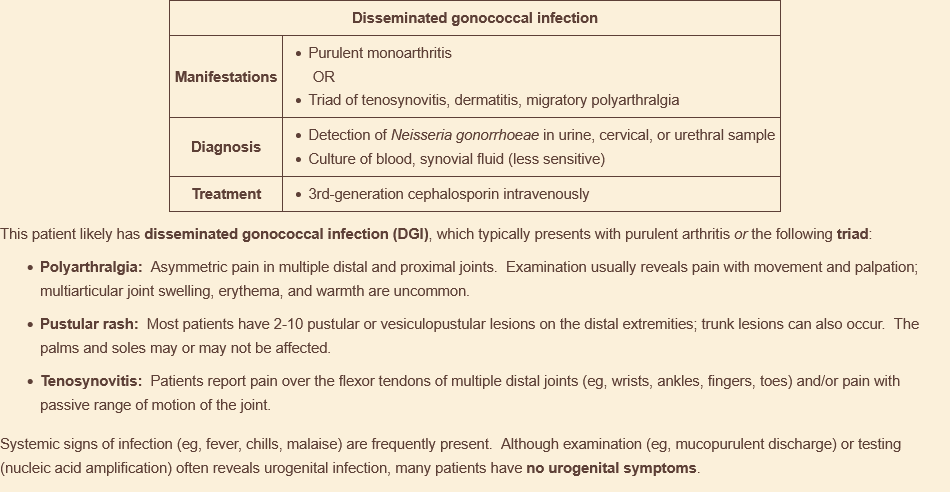

what is the triad of sx for disseminated gonococcal infection?